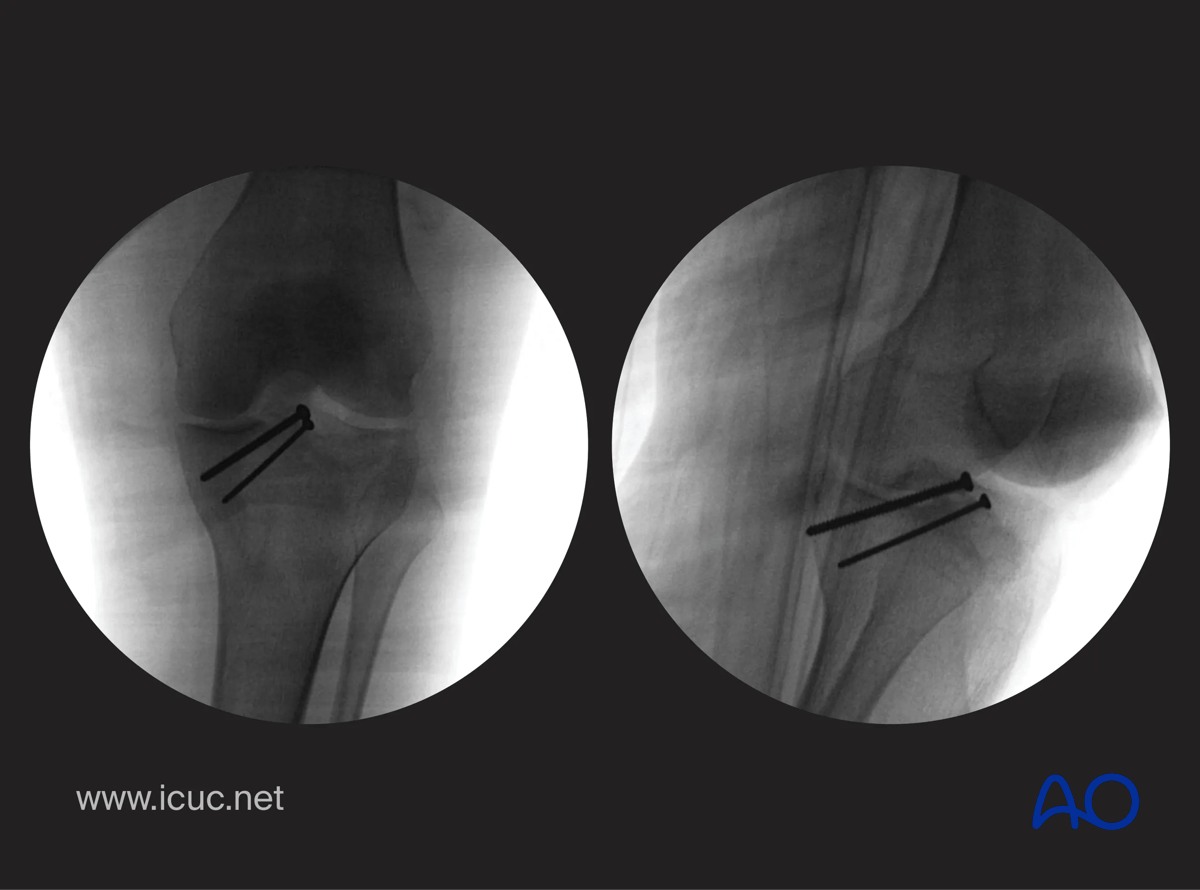

Intraoperative check x-rays in two views.

Avulsion of tibial spine – intraoperative check x-rays in two views